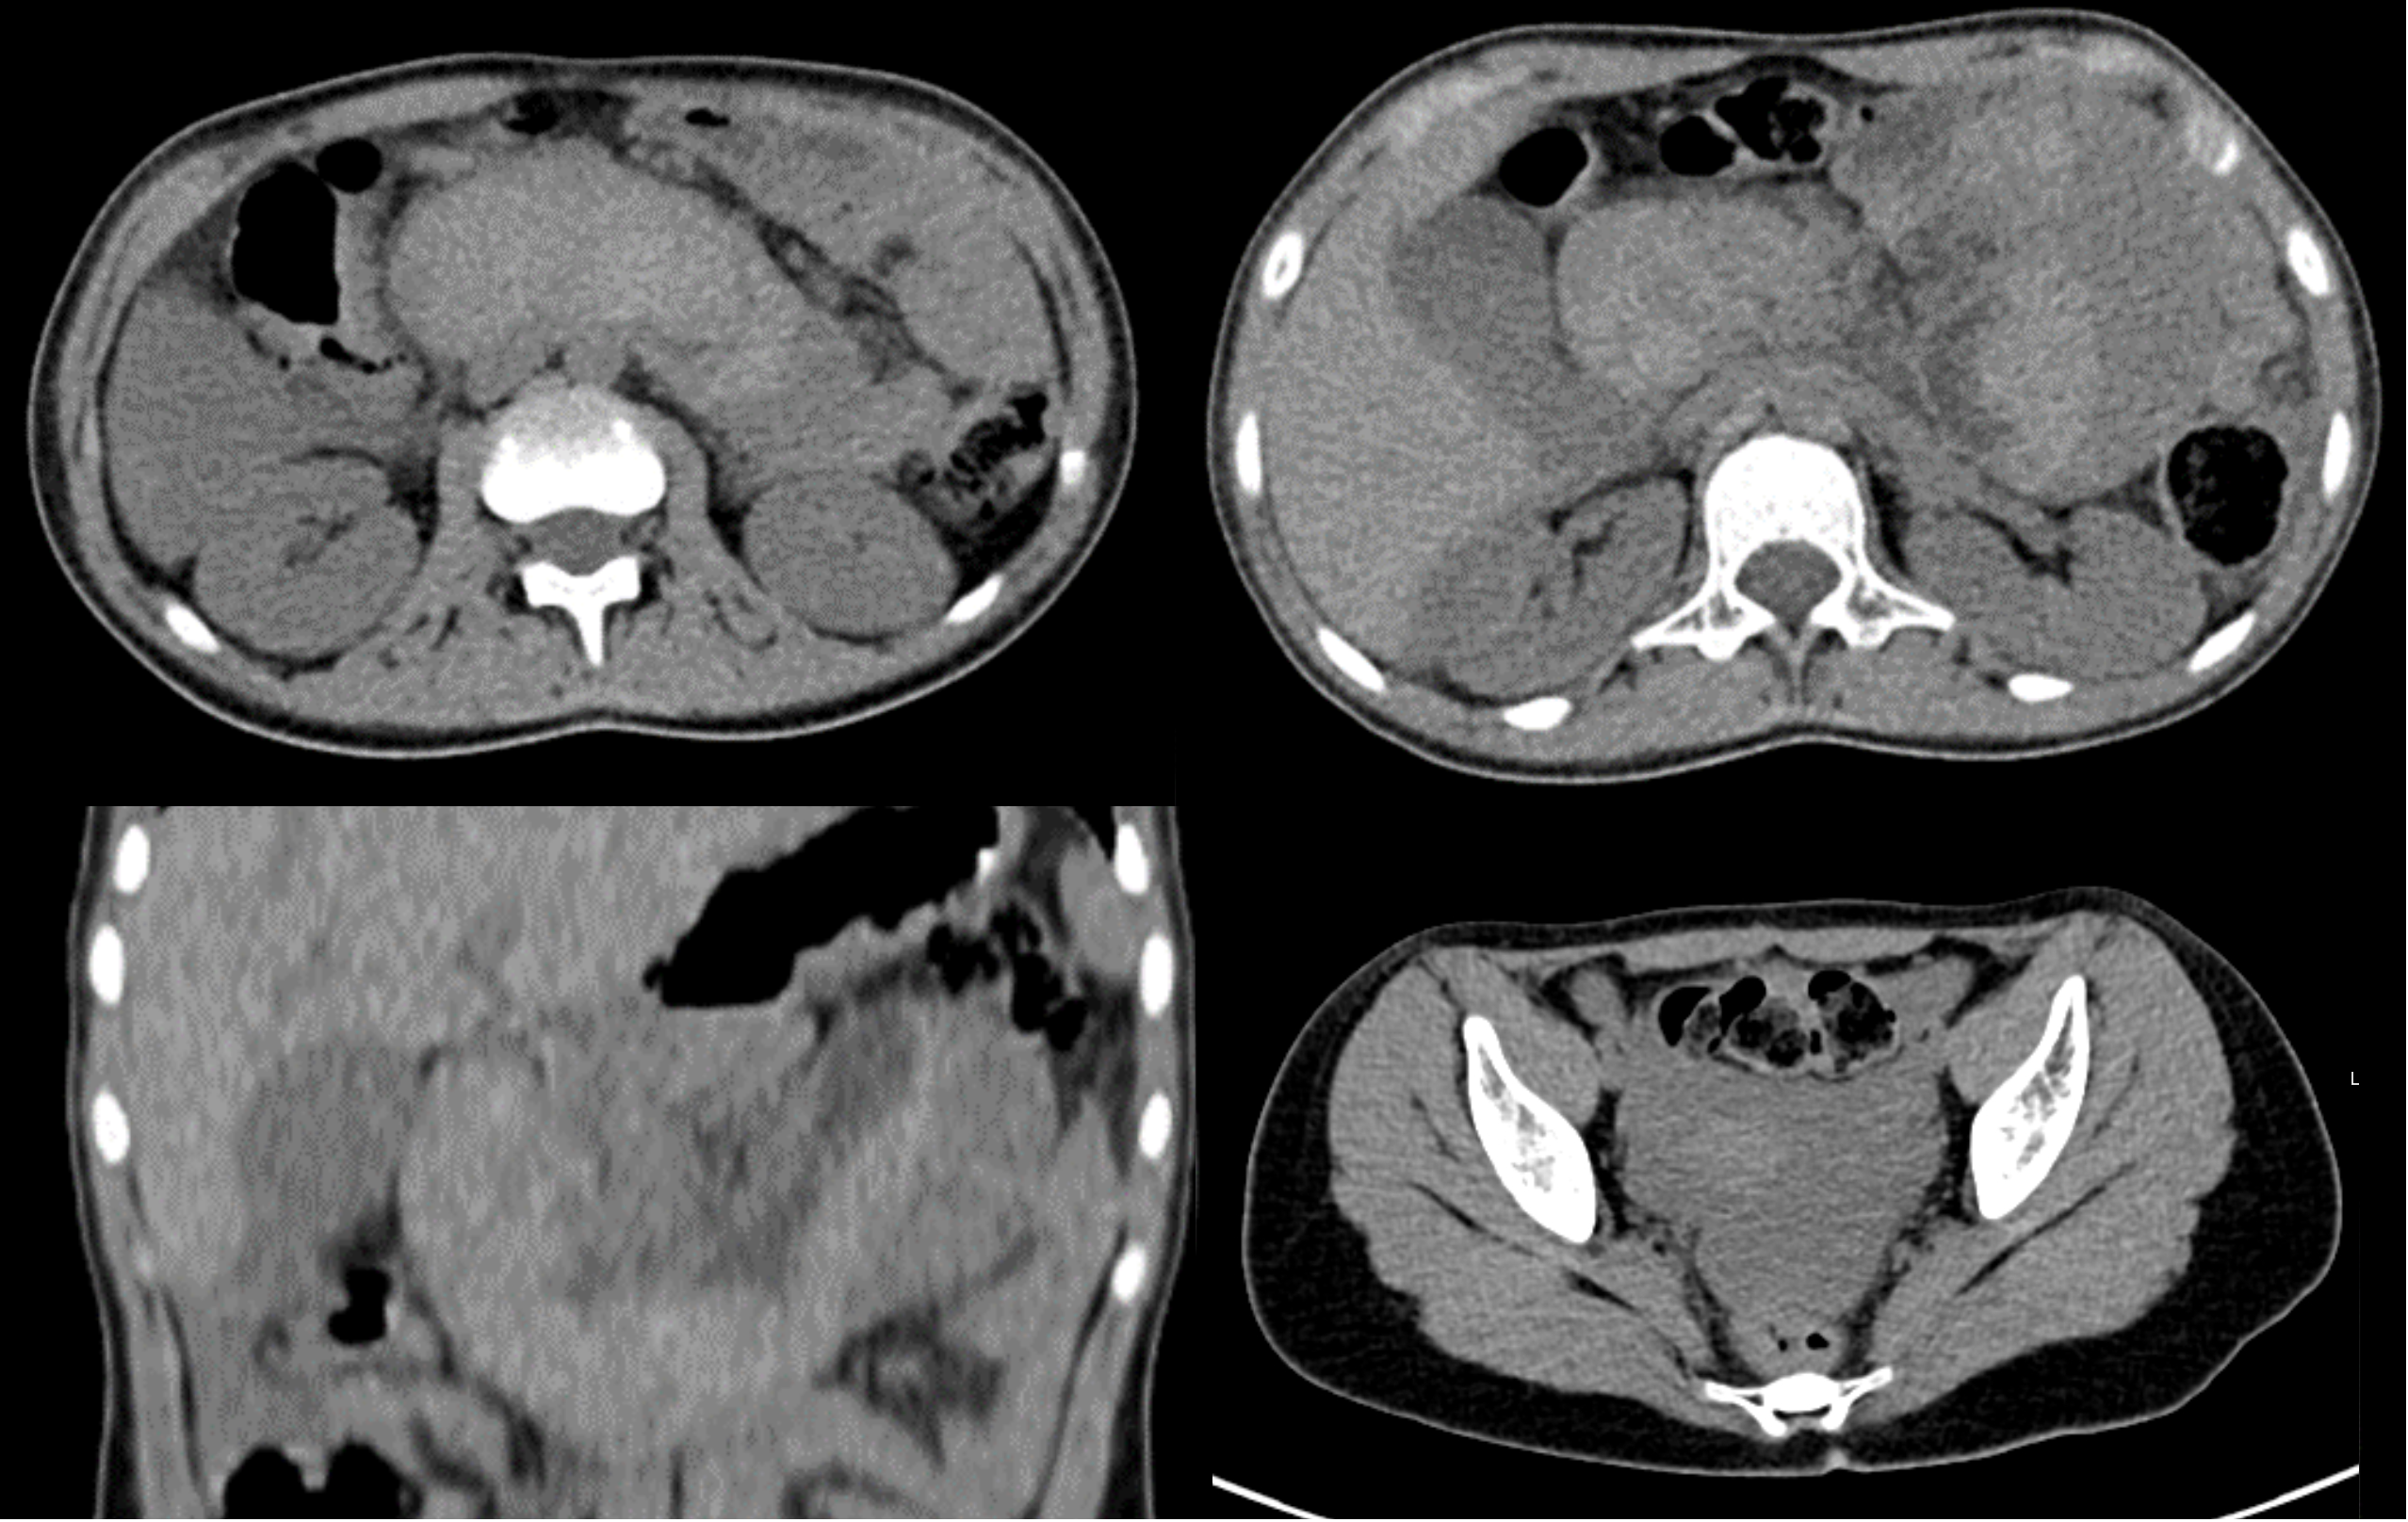

Duodenal hematoma is a rare complication of endoscopic duodenal biopsy, with just a few cases reported in children in the literature available.

The authors present a case of a 13 year-old girl, with a history of Noonan Syndrome and neurofibromatosis type 1, who presented abdominal pain and vomiting after an endoscopic duodenal biopsy.

In this article, we describe the clinical case, imaging findings, evolution and therapeutic approach.